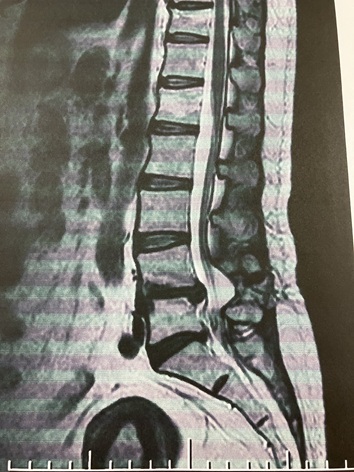

yÇ—á‡@ ‚·‚ׂèÇE’ŊԔƒwƒ‹ƒjƒAEÒ’ŒŠÇ‹·óÇz yÇ—á‡A L5•ª—£Çz

Ç—á‡@‡A‹¤‚ÉAгŽÒ‚³‚ñ‚Í’Pƒ‚Éu˜‚ª’É‚¢v‚Å—ˆ‚ç‚ê‚Ü‚·II

Çó‚àˆÙ‚È‚ê‚ÎA˜’ɂƂµ‚Ă̓¯‚¶Ž¡—Â͂ ‚肦‚È‚¢‚̂Ŗ{Ž¿‚ð–‚¢‚Äs‚«‚Ü‚µ‚傤B